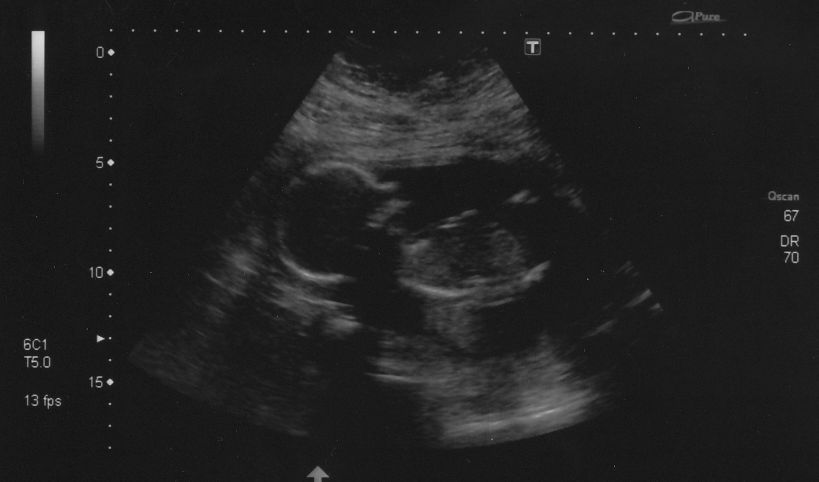

Danyoo wrote:The technician was having a hard time getting measurements because Cody was so active. "If I could just get baby to stop moving for a tenth of a second...I could measure his femur!"